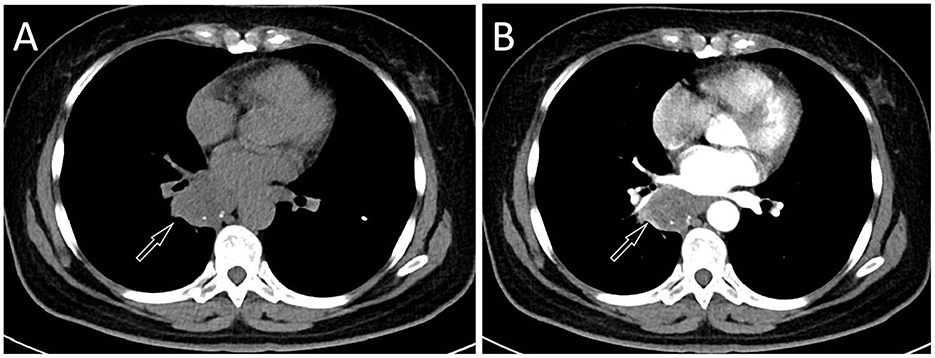

A 57-year-old female patient accidentally discovered a soft tissue mass in her posterior mediastinum during a physical examination in an outside hospital on 11 November 2023. She consciously had no obvious clinical symptoms and was not paid attention to, nor was undergoing any treatment. On 20 April 2024, the patient came to our hospital for medical help due to a cough and chest tightness. The physical examination did not reveal any positive signs. She and her family have denied any history of cancer or major genetic disorders. The serological laboratory test results revealed that the treponema pallidum antibody was positive, while other results, including blood routine, liver and kidney function, and serum tumor markers, were all negative. She had a history of syphilis 15 years ago; the condition resolved completely following treatment, and there are currently no clinical or serological indications of recurrence. She denied any history of tuberculosis, hepatitis, or malignancies. The patient underwent chest computed tomography (CT) examination (Figure 1) on April 24, which revealed a well-defined soft-tissue density mass in the posterior mediastinum with calcification. Contrast-enhanced CT showed a slight enhancement of the mass, suggesting a possible neurogenic tumor. The patient underwent surgical complete resection of the tumor through thoracoscopy under general anesthesia on April 26 after completing the preoperative routine examination. During the operation, the tumor was found to be located between the spine, azygos vein, trachea, and esophagus, with a size of approximately 6 cm × 4.5 cm × 4.0 cm, spindle-shaped, with a complete capsule and no obvious adhesion to surrounding structures. The tumor was gradually separated along its edges using an ultrasonic knife until it was completely removed, and then sent for pathological examination. Hematoxylin–eosin staining (as shown in Figure 2) showed that the excised tumor tissue appeared as a gray–red envelope block with intact capsule, medium texture, and calcified lesions in some areas. No tumor invasion was observed at the resection margin. Immunohistochemistry revealed tumor cells positively expressed vimentin, Cluster of Differentiation 34 (CD34), cytokeratin (CK), and CD56, while they negatively expressed insulinoma-associated protein 1 (INSM1), S100, CD68, and so on. Based on these histopathological findings of the patient, she was diagnosed with PES. After surgery, the patient did not receive further radiotherapy, chemotherapy, or other treatment methods. At 4 months after discharge, a chest CT examination revealed a new soft tissue density nodule at the site of her previous surgery. In order to further evaluate the nature of the nodule and determine the next treatment plan, the patient underwent 18F-FDG PET/CT imaging (as shown in Figure 3) on August 20. The results showed that the above nodule, as shown on CT, showed a significantly increased 18F-fluorodeoxyglucose (18F-FDG) uptake, while no significant hot spots were observed in the rest of the body. These imaging findings suggested the possibility of local recurrence of the tumor, and due to the limitation of the lesion, the surgeon planned to perform a second operation on her. However, the patient refused surgery again. On October 16, the patient returned to the hospital for chest pain and underwent chest CT examination (Figure 4), which showed that the mass was significantly larger than before. Currently, she is receiving a chemotherapy regimen of epirubicin in combination with isocyclophosphamide.

Figure 1

Chest computed tomography (CT) mediastinal window (A) revealed a soft tissue density mass (black arrow) about 4.6 cm × 3.2 cm in size with nodular calcification (red arrow) can be observed on the right posterior mediastinum; (B) The coronal view shows that the tumor is spindle shaped (arrow); In the arterial phase (C) and vein phase (D) of contrast-enhanced CT, the lesion showed mild uneven enhancement (arrows); In the delayed phase (E, axial, F, sagittal), the enhancement of the mass gradually diminishes (arrows).

The patient's chest CT 6 months after surgery, CT plain scan (A) and contrast-enhanced CT (B) revealed a significant increase in the volume of the mass, with a maximum cross-sectional area of about 4.7 cm × 3.9 cm.